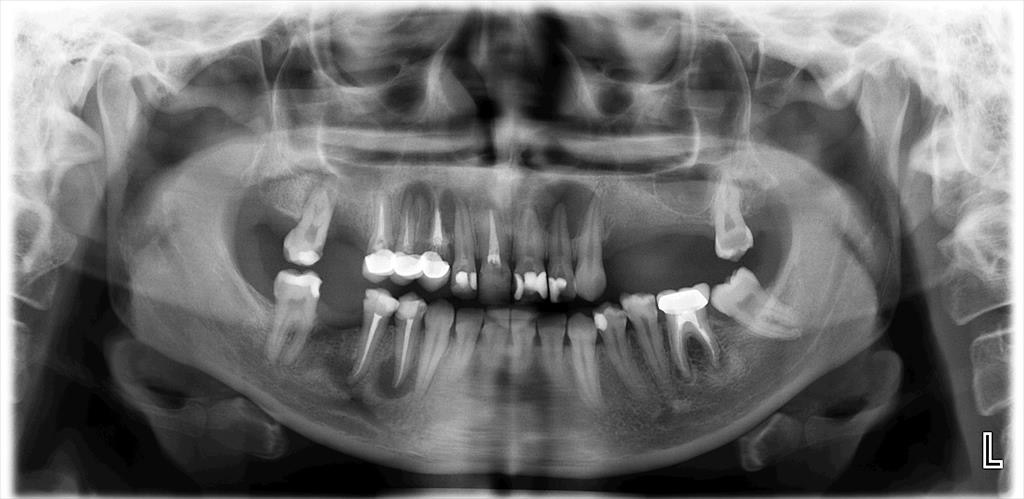

The diagnosis of AP was confirmed by clinical and radiographic examinations. All types of AP, including asymptomatic AP, symptomatic AP, acute apical abscess, and chronic apical abscess were considered. All radiographic images were obtained using the same imaging system (Planmeca Promax; Planmeca, Helsinki, Finland). If the periapical tissue was normal or had minimal changes in bone structure, the related tooth was classified as healthy (PAI 1 and 2), according to the periapical index (PAI).19 In the event of a lost periodontal ligament or periodontitis with exacerbating features (PAI 3, 4 and 5), the tooth was classified with a periapical pathology.20 The PAI score for multi-rooted teeth was determined based on the highest score observed across all roots.21

Digital panoramic radiographs were taken and analyzed by an endodontist and an experienced dentist (Figure 1,Figure 2). Both observers were blinded to the study groups. In cases of disagreement, the analysis was repeated. After the radiographic analysis, pulp sensitivity, percussion and palpation tests were performed to confirm the clinical diagnosis of AP. Patients with at least 1 tooth exhibiting signs of AP were included in the AP group.